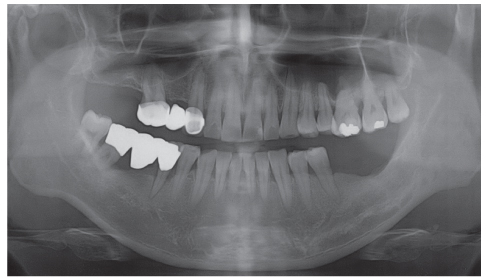

Figure 3

Periapical view taken 2 years ago.

Figure 3 Periapical view taken 2 years ago.